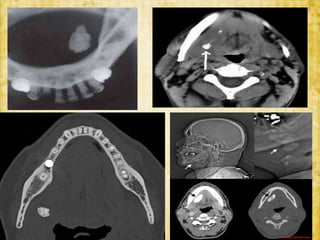

• Radiographs :- AnteroPosterior view

- lateral oblique

- occlusal view

INVESTIGATIONS • Radiographs :-AnteroPosterior view - lateral oblique - occlusal view • Sialography : specialized radiographic method involving filling of ducts and parenchyma with a radiopaque agent and make them visible on a radiograph.